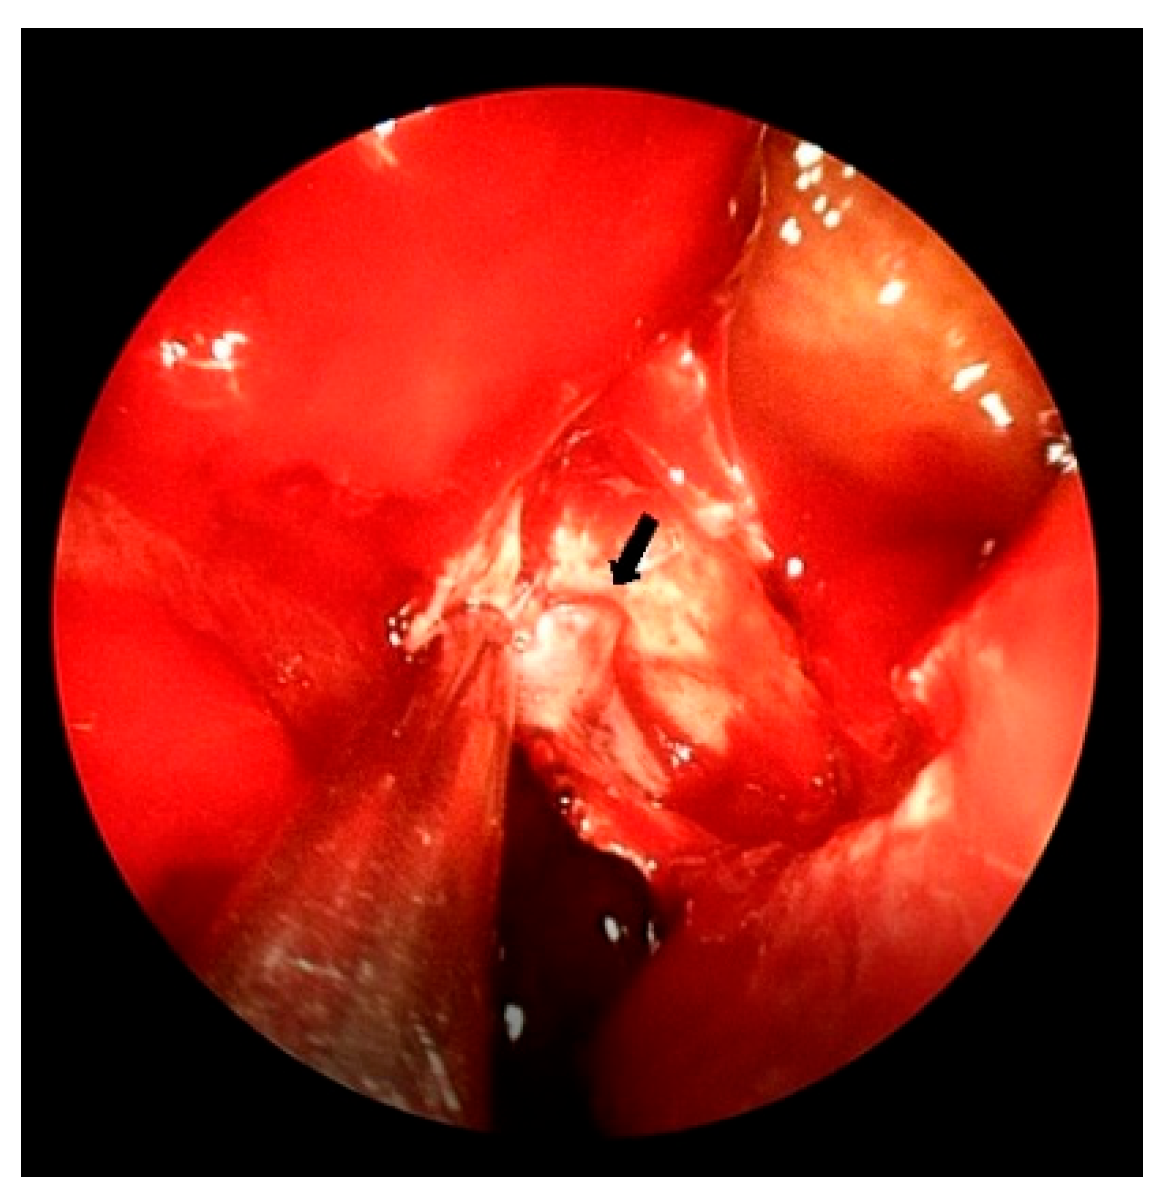

All operative procedures were performed under general anesthesia. In this patient, septoplasty was performed in order to help identify the bleeding focus. The nasal septum was deviated and an uncinectomy and middle meatal antrostomy were conducted in order to remove the hematoma on the left maxillary sinus. Anterior ethmoidectomy was performed and a large hematoma was observed. Bleeding along the left Fossa of Rosenmüller in the nasopharynx to the pharynx was also noted. Following the incision over the posterior fontanelle, the mucoperiosteal flap was elevated and dissected with a freer elevator just posterior to the vertical ridge of the middle meatal antrostomy. Crista ethmoidalis was noted anterior to the upper section of the flap, and the SPA main trunk exiting at the sphenopalatine foramen (SPF) was identified posterior to the crista ethmoidalis (Figure 2); electrocautery was performed. The posterior nasal artery (PNA) and septal artery branching from the main trunk were also identified and cauterized together. After arresting the bleeding, a nasal pack with NasoPore® and a carbosymethyl cellulose sheet (Rhinocel®) were inserted. The nasal packing was removed on the first postoperative day and no active bleeding was observed. Postoperatively, the patient suffered from; aspiration pneumonia, pleural effusion, lower extremity edema, ear fullness, and nasal crust for several days. There was no postoperative bleeding noted and her hemodynamic state was stable. After medical treatment, the patient was discharged. One month postoperatively, there was no recurrence of epistaxis. As illustrated in Figure 3, the patient’s clinical course progressed from initial misdiagnosis as upper gastrointestinal bleeding to definitive diagnosis of posterior epistaxis, followed by successful ESPAL.

Figure 2. Endoscopic exposure of the left sphenopalatine artery (arrow) exiting from the sphenopalatine foramen.